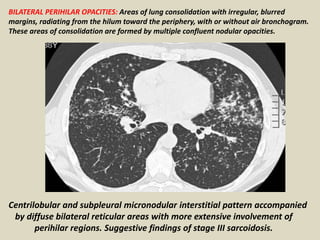

BILATERAL PERIHILAR OPACITIES: Areas of lung consolidation with irregular, blurred

margins, radiating from the hilum toward the periphery, with or without air bronchogram.

These areas of consolidation are formed by multiple confluent nodular opacities.

Centrilobular and subpleural micronodular interstitial pattern accompanied

by diffuse bilateral reticular areas with more extensive involvement of

perihilar regions. Suggestive findings of stage III sarcoidosis.